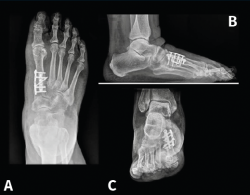

Figura 13. Caso del Dr. Martín Ferreyra. Imágenes radiológicas preoperatorias. A: dorsoplantar; B: perfil; C: axial de los sesamoideos.

Figura 14. Caso del Dr. Martín Ferreyra. Imágenes radiológicas postoperatorias. A: dorsoplantar; B: perfil; C: axial de los sesamoideos. Obsérvese la corrección obtenida y la ubicación de los sesamoideos antes y después de la cirugía.

Es por ello que en la actualidad autores como E. y P. Wagner(68) realizan una osteotomía tridimensional, no solo en el plano transversal, a la que denominan PROMO. En el caso de la artrodesis cuneometatarsiana sucede lo mismo y una de las tendencias actuales es realizar un Lapidus modificado tridimensional(69,70), como puede verse en el caso de M. Ferreyra (Figuras 13 a 15), en el que la estabilización con 2 placas permite una carga precoz.

Figura 15. Caso del Dr. Martín Ferreyra. Imágenes clínicas. A: preoperatorio; B: postoperatorio.